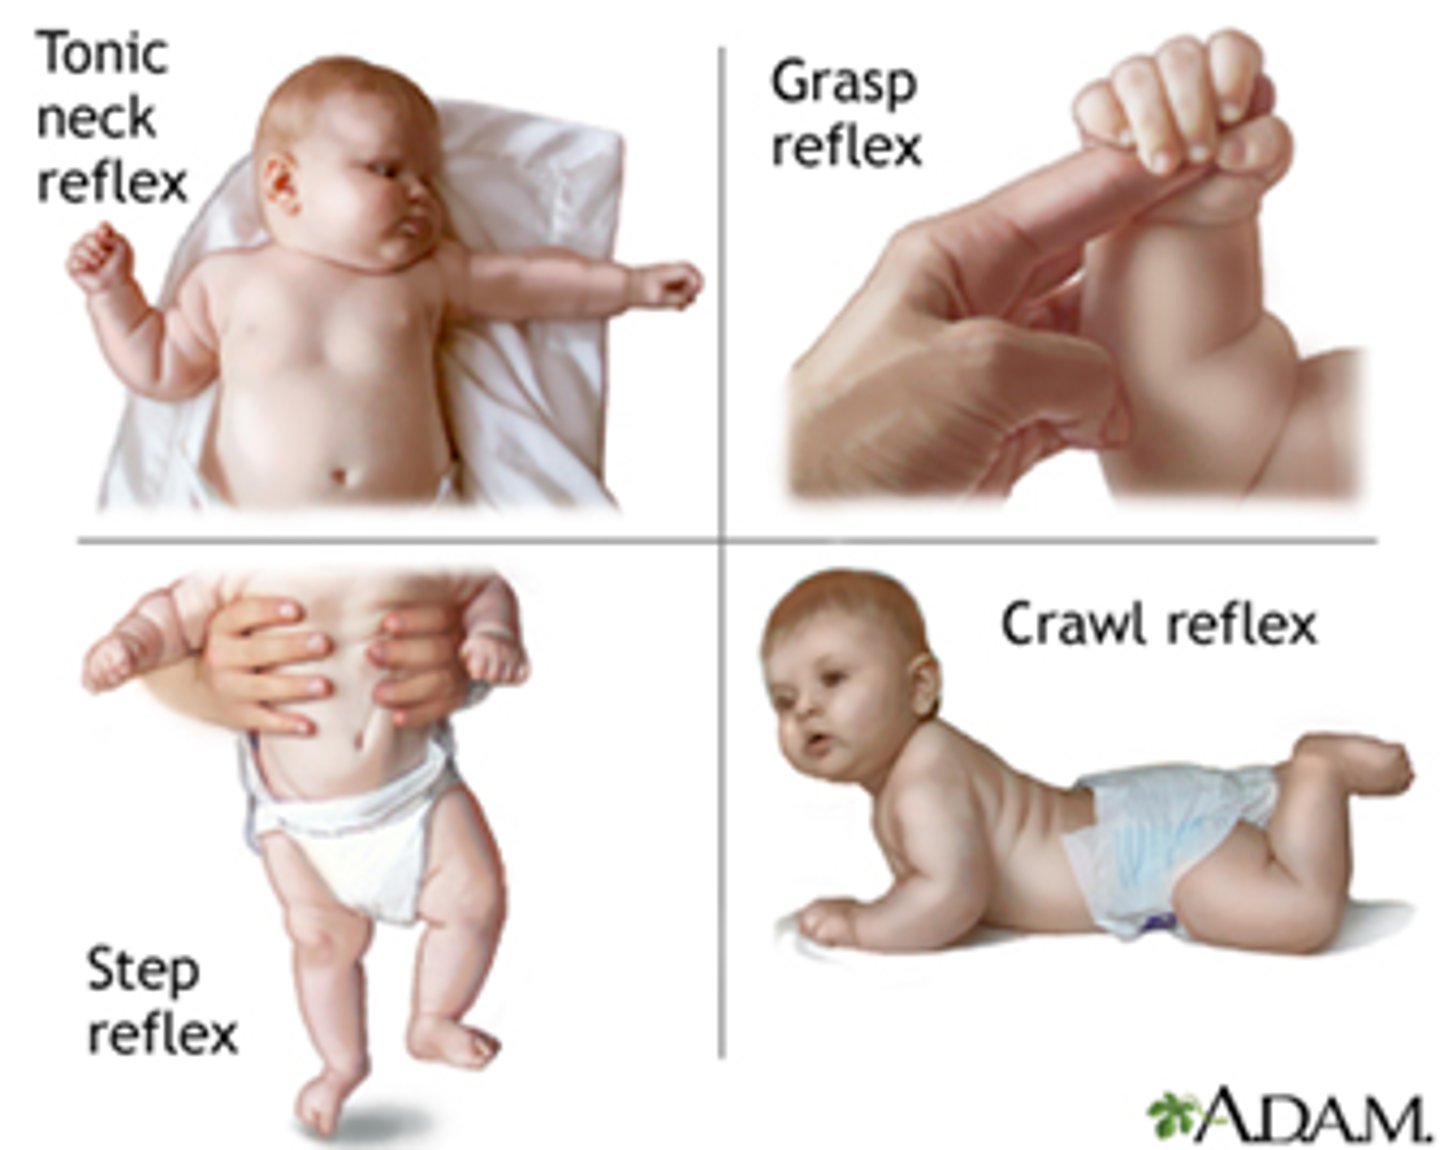

development of reflexes (2 types)

innate and acquired

innate reflexes

basic neural reflexes formed before birth (sucking, baby grabbing your finger if you put it in their hand)